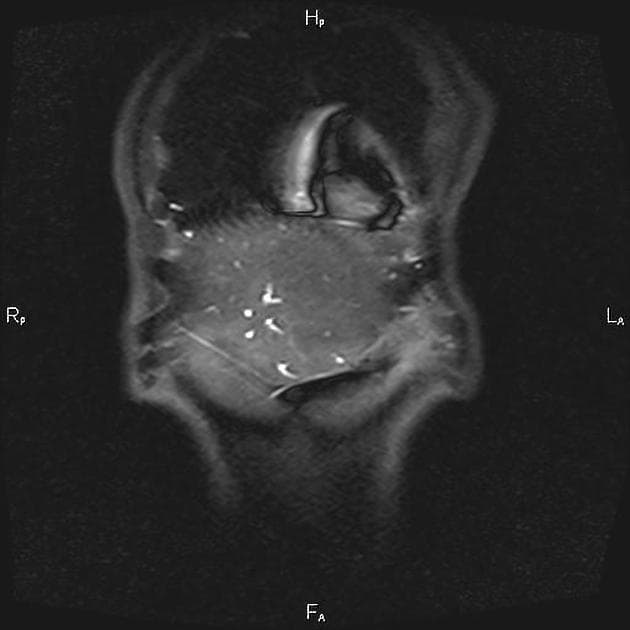

Coronal T2

- Có giãn dạng thoi các ống mật ngoài gan (bao gồm ống mật chủ và ống gan chung) chứa nhiều ổ giảm tín hiệu trên mọi chuỗi xung, phân bố theo trọng lực, phù hợp với hình ảnh sỏi.

- Không có giãn đường mật trong gan.

- Có một tổn thương nhỏ dạng nang (tín hiệu cao trên T2, thấp trên T1 và không ngấm thuốc) ở đầu tụy, thông với một nhánh ống tụy nhỏ, phù hợp với IPMN nhánh bên (side branch IPMN).

- Không giãn ống tụy chính.

- Không thấy thành phần tăng mật độ có ngấm thuốc.

Interpretation: U nang ống mật chủ (type 1) kèm theo tổn thương IPMN nhánh bên phát hiện tình cờ (incidental side branch IPMN).

U nang ống mật chủ - type I (choledochal cyst - type I)